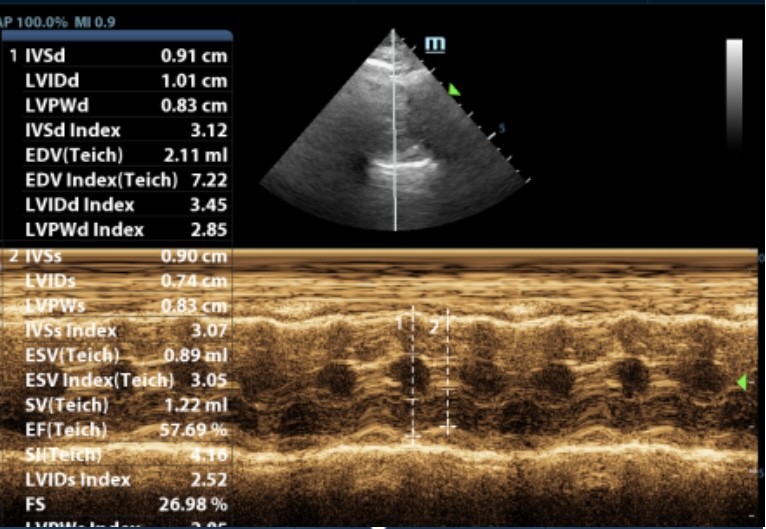

心脏疾病是老年宠物常见的健康问题,医院配备了进口心脏彩超设备,能够精准诊断各种心脏疾病。负责心脏科的张培培医生擅长心肌病、肥厚型心肌病等复杂心血管疾病,并提供长期药物管理和定期随访服务,帮助宠物维持良好的心脏功能。

此前,6岁的猫咪因抽搐呕吐,后腿无力就诊,经查后发现左心室心肌及室间隔厚度增加,主动脉和二尖瓣均存在反流,诊断为肥厚型心肌病。口服利尿剂和抗血栓药物,一周后精神好转,再无出现抽搐、呕吐、后腿无力等现象。